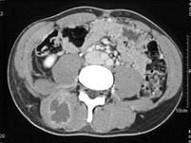

问题 女,28岁,右肾区痛伴高热,请根据所示图像,选择最可能诊断 ( )

选项 A、右侧输尿管下段结石 B、右侧脊柱旁脓肿 C、右侧输尿管上段结石 D、右侧输尿管中段结石 E、右肾结石

答案 B